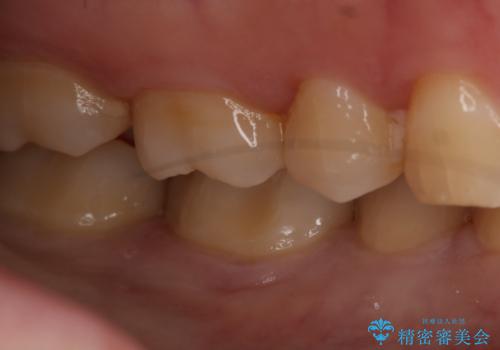

- 右下奥歯の虫歯治療を希望された患者様です。

保険の材料が劣化し、直下で虫歯の存在が確認出来ました。

セラミックを希望されたので形態・切削量を考慮し、セラミックインレーでの治療を計画しました。

虫歯が広く進行していましたが神経には到達していなかったので、予定通りセラミックインレーでの治療を行いました。